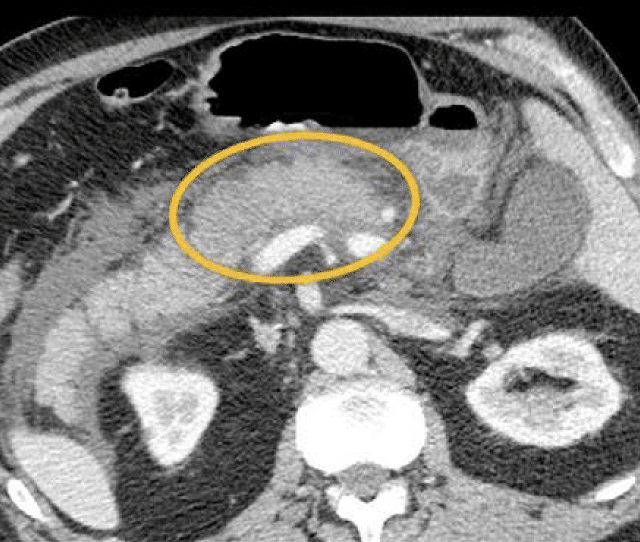

Surenth starter pr. 1. september 2023 i PhD stilling omhandlende pancreasforskning. og så skal der stå en sætning mere her, før at layoutet passer. Læs mere her